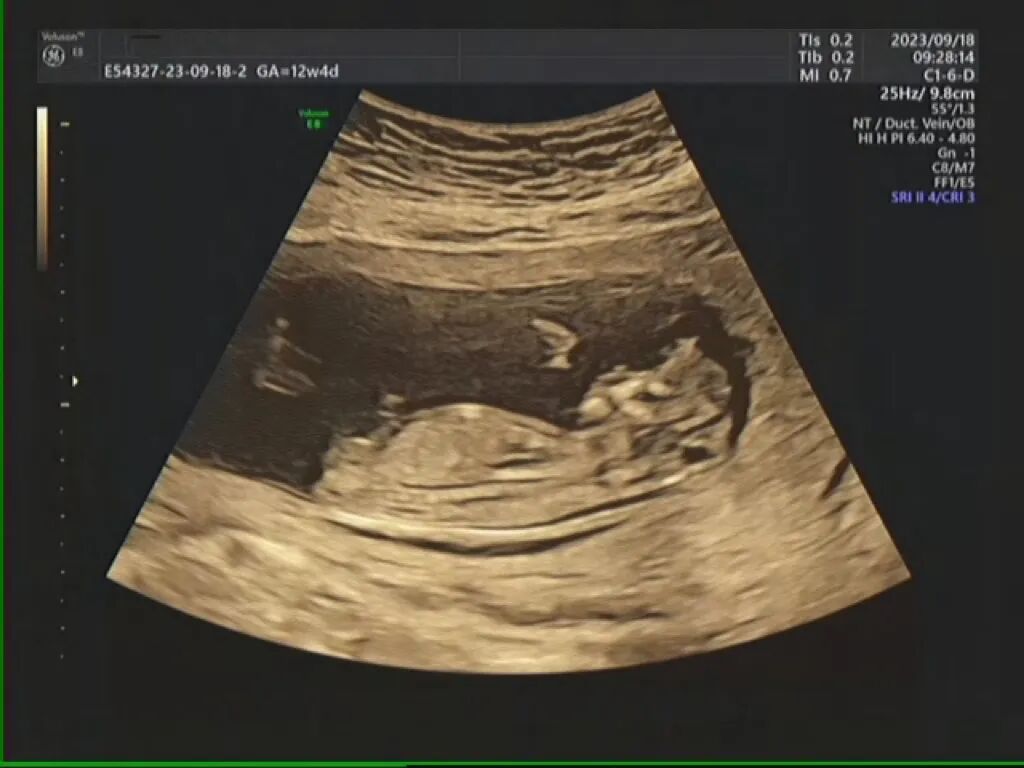

李女士是在妊娠12+4周时,在当地医院查出胎儿超声异常的,初次怀孕的她非常紧张、焦虑,随即慕名转诊至福建省妇幼保健院,复查针对性彩超结果提示:后壁胎盘,A胎发育AUA13w3d;B胎发育AUA13w3d,B胎露脑畸形,随访观察1周后复查。(露脑畸形:胎儿露脑畸形指的是胎儿颅骨缺失,脑组织只有脑膜覆盖的情况。)

等到妊娠15+5周,李女士再次复查彩超提示:A胎发育AUA16w4d;双侧脑室脉络丛囊肿;B胎发育AUA16w5d,无脑儿。